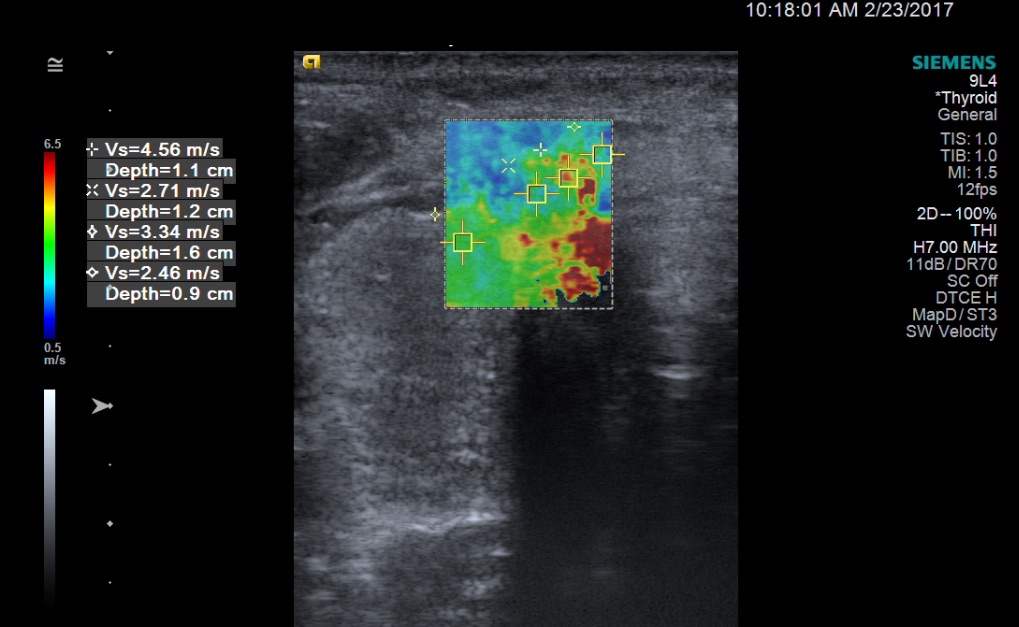

In the lateral aspect of the left lobe was a 1.1-cm, isoechoic solid nodule with rim shadowing calcifications, a taller-than-wide shape, and mildly increased internal vascularity. Routine SWE was performed using Virtual Touch imaging on a Siemens ACUSON S2000 ultrasound system. The right nodule had 2 areas of high SWV measuring 3.88 m/s and 2.07 m/s; the surrounding thyroidal tissue had a SWV of 2.06 m/s. The isthmus nodule exhibited higher SWV in the medial aspect, with an area measuring 4.56 m/s; the lateral aspect of the nodule had a SWV of 2.71 m/s; and the surrounding thyroidal tissue had a SWV of 2.46 m/s (Figure 3).

Figure 3. SWE image (soft tissue in blue, stiffer tissue in red) with quantitative SWV measurements of the isthmus nodule. In the medial aspect of the isthmus nodule is an area that exhibited a high SWV of 4.56 m/s. The lateral aspect of the nodule had a SWV of 2.71 m/s, and the surrounding thyroidal tissue had a SWV of 2.46 m/s.